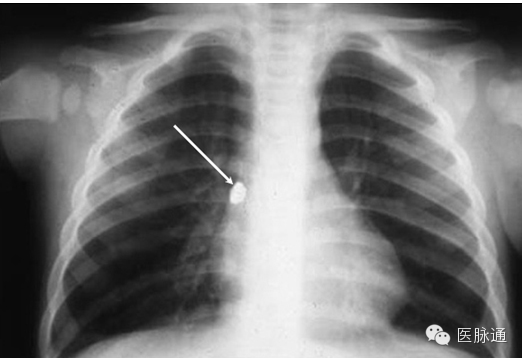

气道异物最常见于儿科患者。异物最常见部位是右主支气管,这是由于其位置偏后,与主气管的角度较小,且直径较粗。异物密度决定其在胸片上是否可被鉴别。气道异物的间接征象包括:若异物造成部分梗阻,可出现局灶性过度充盈;若完全梗阻,则出现肺不张。图5(箭头)显示一枚耳环嵌在一名儿童右主支气管。

图5